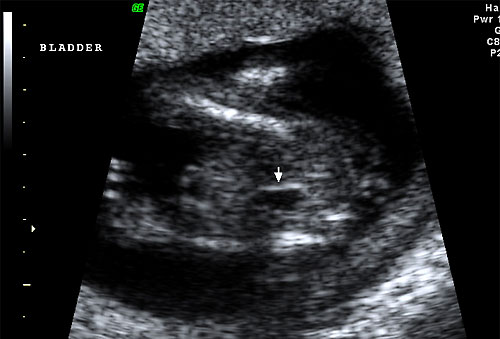

Normal 16 week fetal bladder |